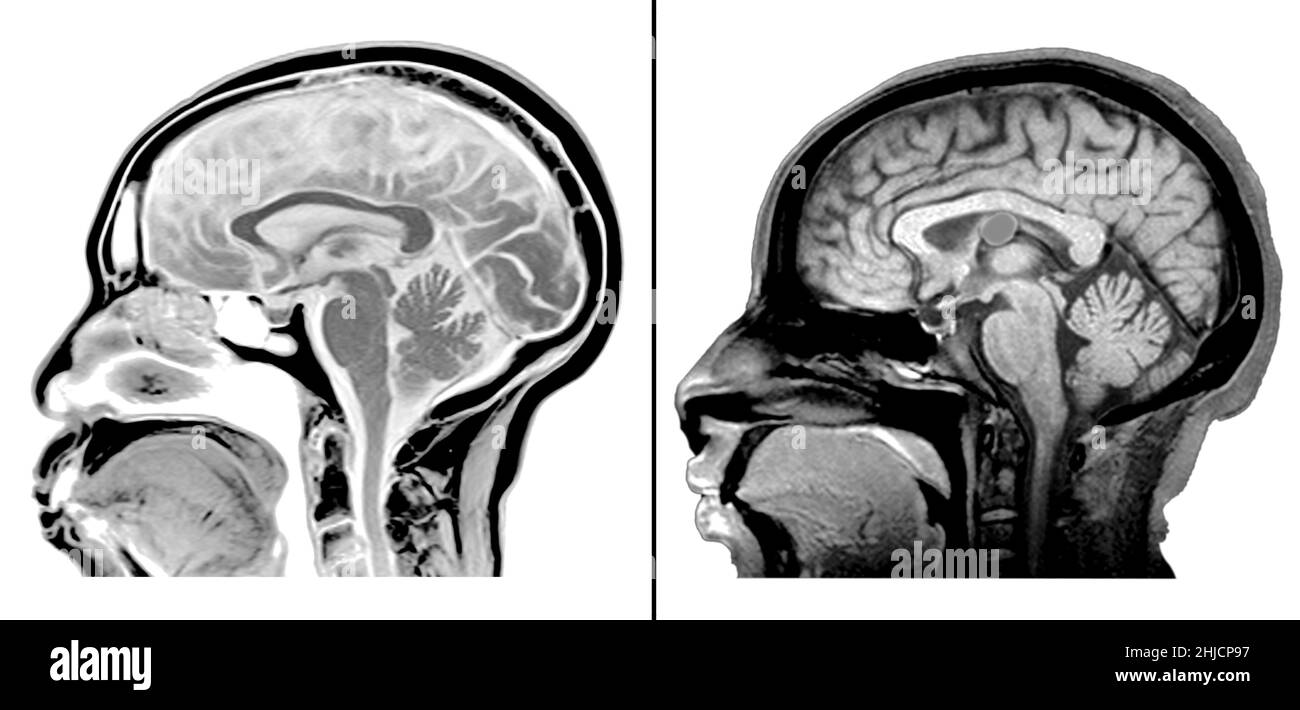

Als Kolloidzyste wird eine gutartige zystische Struktur bezeichnet, die typischerweise im Bereich des dritten Hirnventrikels auftritt. Kolloidzysten können das Foramen Monroi verlegen, was zu einem Liquoraufstau mit Hydrozephalus führt. Symptomatische Kolloidzysten werden neurochirurgisch häufig minimalinvasiv neuroendoskopisch entfernt. Bei asymptomatischen (beschwerdefreien) Kolloidzysten, bei denen es sich nicht selten um Zufallsbefunde handelt, kann die Operationsindikation erwogen werden, wenn die Größe geeignet erscheint, das Foramen Monroi zu verlegen. Plötzliche Todesfälle in Zusammenhang mit vorher asymptomatischen Kolloidzysten sind in Einzelfällen beschrieben worden.